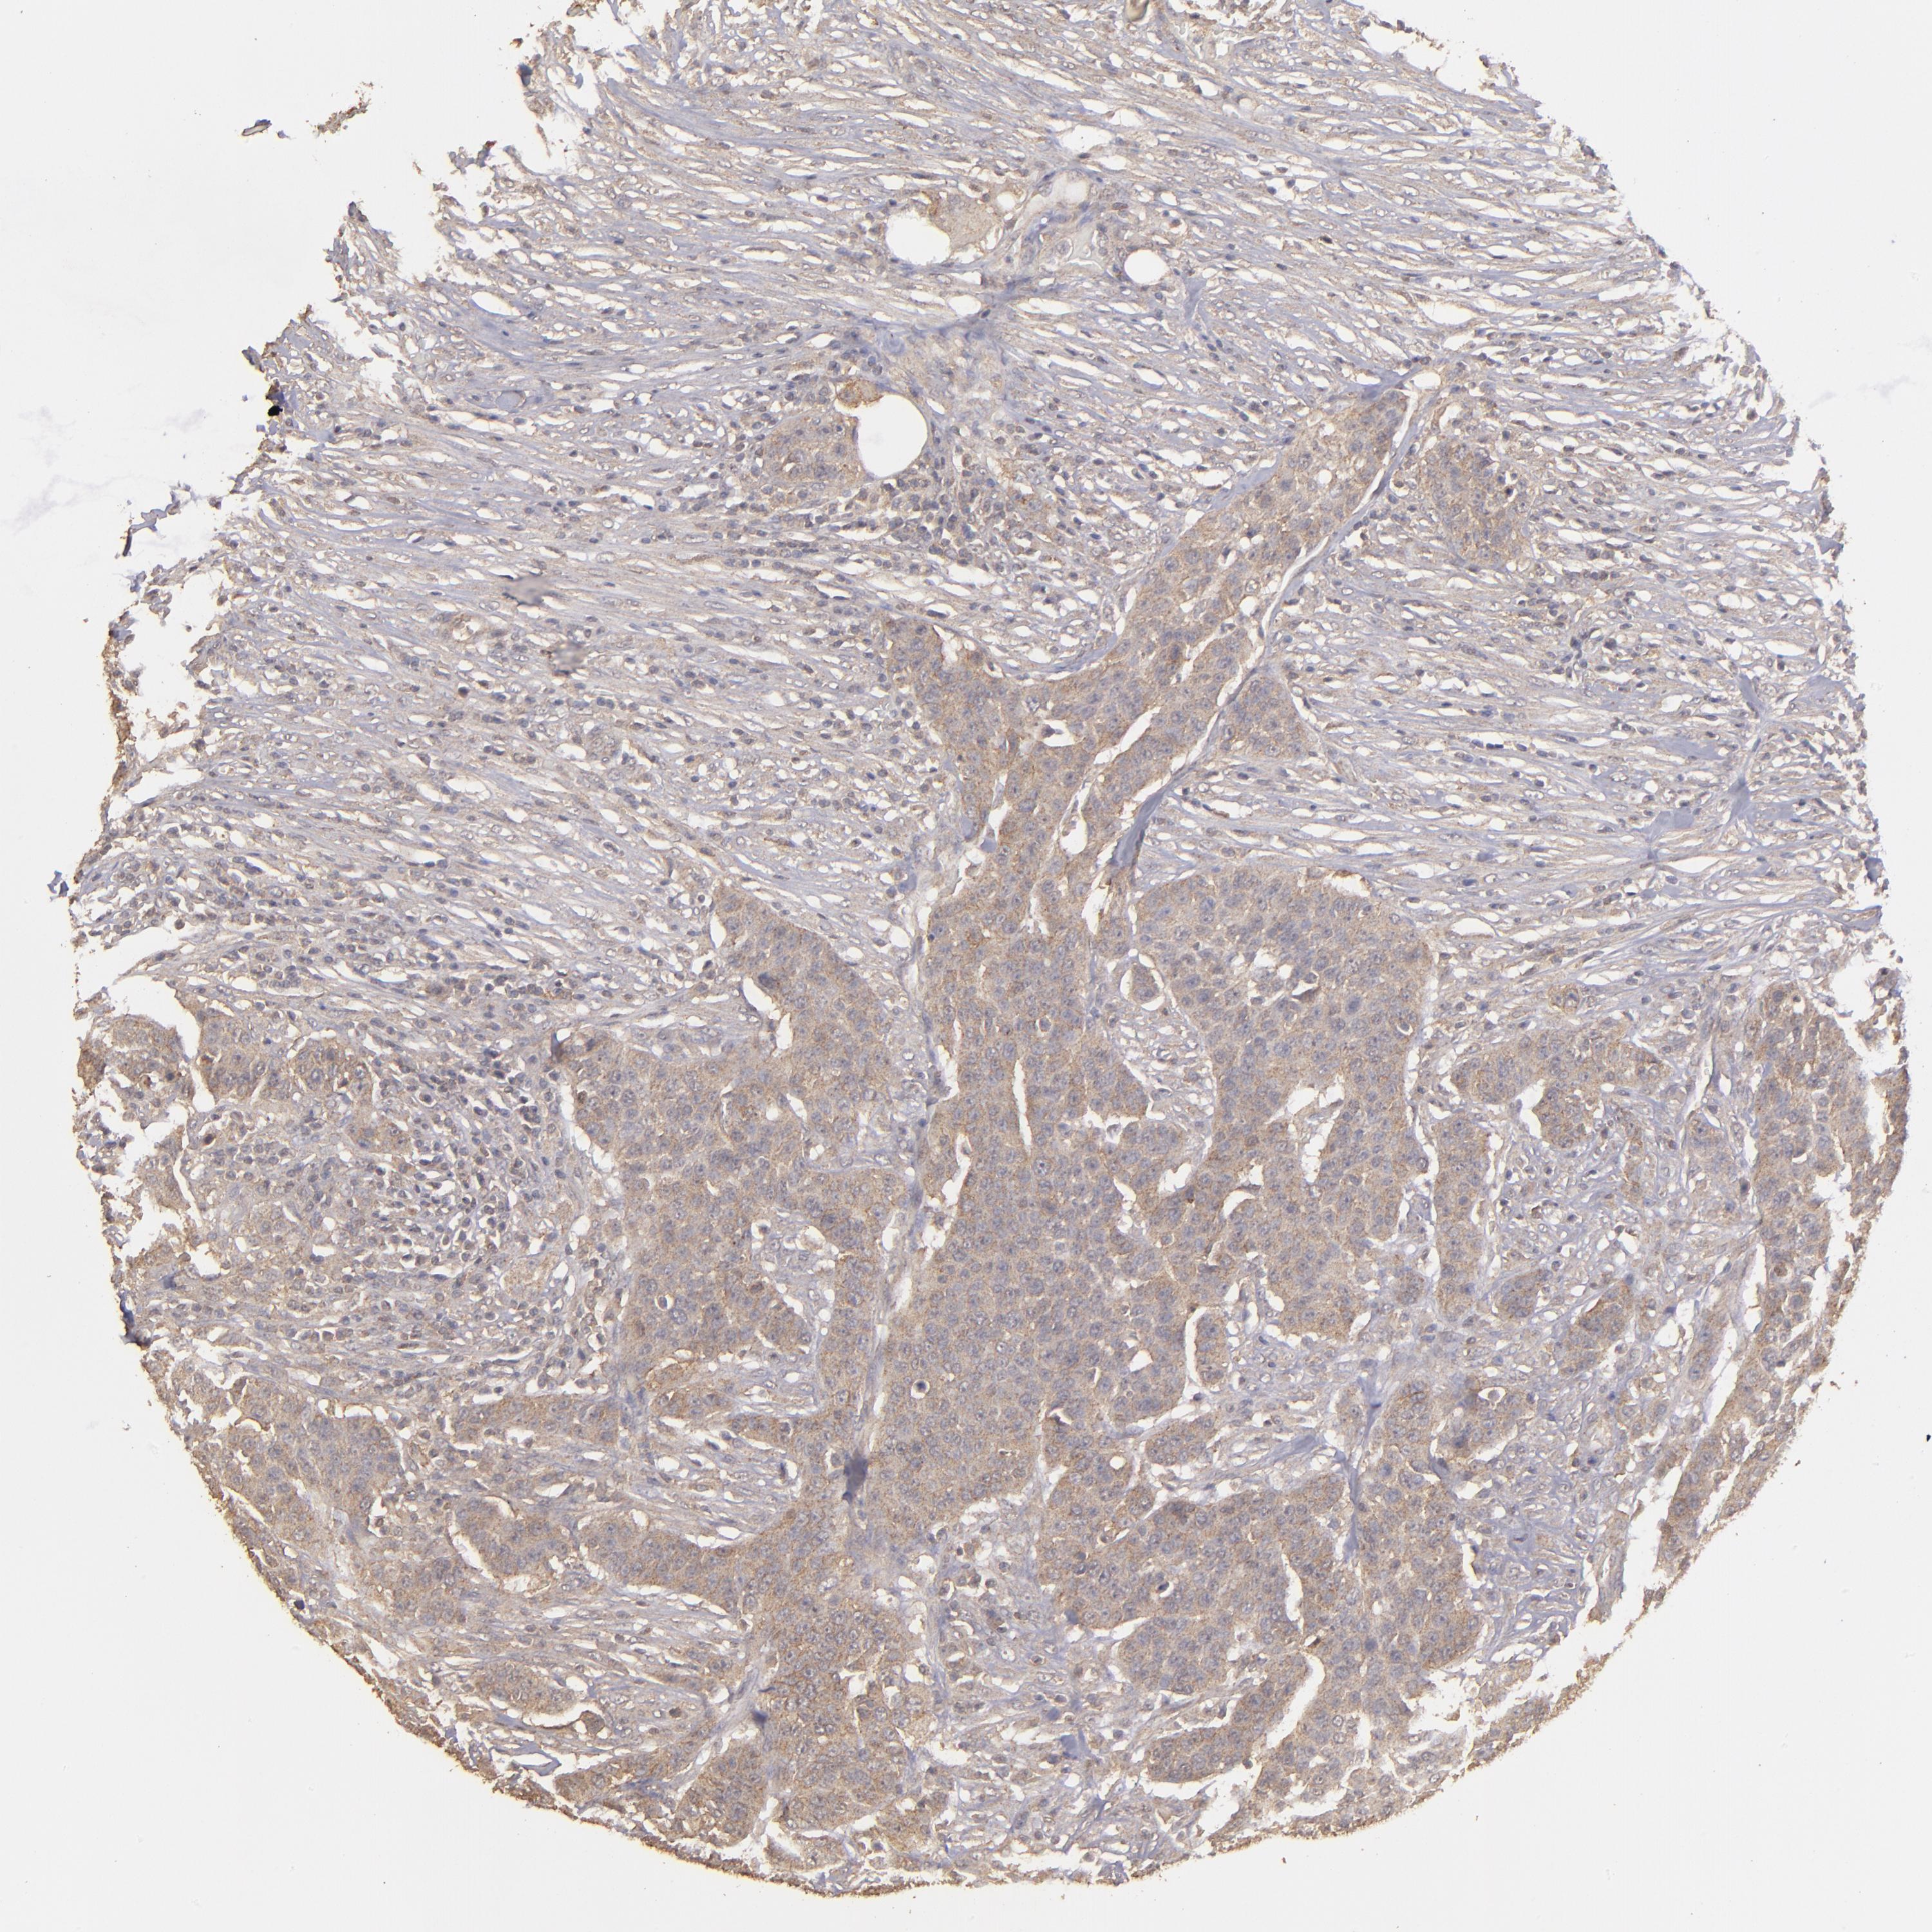

UROTHELIAL CANCER - Protein expressioni

A mouse-over function shows sample information and annotation data. Click on an image to view it in a full screen mode. Samples can be filtered based on level of antibody staining by selecting one or several of the following categories: high, medium, low and not detected. The assay and annotation is described here.

Note that samples used for immunohistochemistry by the Human Protein Atlas do not correspond to samples in the TCGA dataset.

Antibody stainingi

Antibody staining in the annotated cell types in the current human tissue is reported as not detected, low, medium, or high, based on conventional immunohistochemistry profiling in selected tissues. This score is based on the combination of the staining intensity and fraction of stained cells.

Each image is clickable and will lead to virtual microscopy that enables deeper exploration of all samples and also displays staining intensity scores, fraction scores and subcellular localization as well as patient and tissue information for each sample.

Antibody HPA001869

Antibody HPA023882

Staining

High

Medium

Low

Not detected

Intensity

Strong

Moderate

Weak

Negative

Quantity

>75%

75%-25%

<25%

None

Location

Nuclear

Cytoplasmic/membranous

Cytoplasmic/membranous,nuclear

Urothelial carcinoma, High grade

Urothelial carcinoma, Low grade